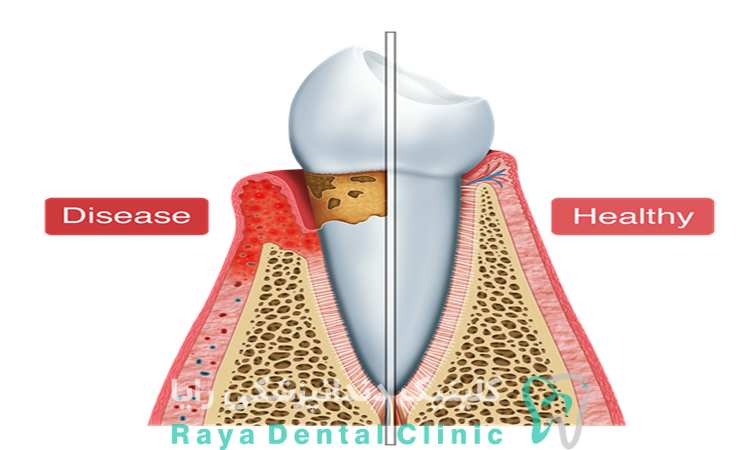

عقب رفتن لثه ها بدون درد به حالتی گفته می شود که بافت لثه به تدریج از روی سطح دندان به سمت پایین یا عقب جابه جا می شود، بدون اینکه فرد در مراحل اولیه احساس ناراحتی یا درد داشته باشد. این وضعیت معمولاً نشان دهنده شروع یک فرایند تخریبی آهسته در بافت های نگهدارنده دندان است و ممکن است ریشه دندان را در معرض محیط دهان قرار دهد.

در بسیاری از موارد، تحلیل لثه بدون درد به دلیل التهاب مزمن، فشارهای مکانیکی ناشی از مسواک زدن نادرست، تجمع پلاک میکروبی یا عوامل ژنتیکی رخ می دهد. از آنجا که روند این عارضه تدریجی است، تشخیص زودهنگام آن اهمیت زیادی دارد تا از پیشرفت آسیب و مشکلات جدی تر جلوگیری شود.

- تجمع پلاک و التهاب مزمن لثه: فعالیت باکتری ها در خط لثه باعث تخریب بافت نگهدارنده می شود، حتی اگر درد واضحی احساس نشود.

- بیماری های لثه ای اولیه: مراحل ابتدایی بیماری های پریودنتال ممکن است بدون درد پیشرفت کنند.

- بیماری های پریودنتال مزمن: التهاب طولانی مدت لثه که باعث تخریب بافت نگهدارنده دندان می شود.